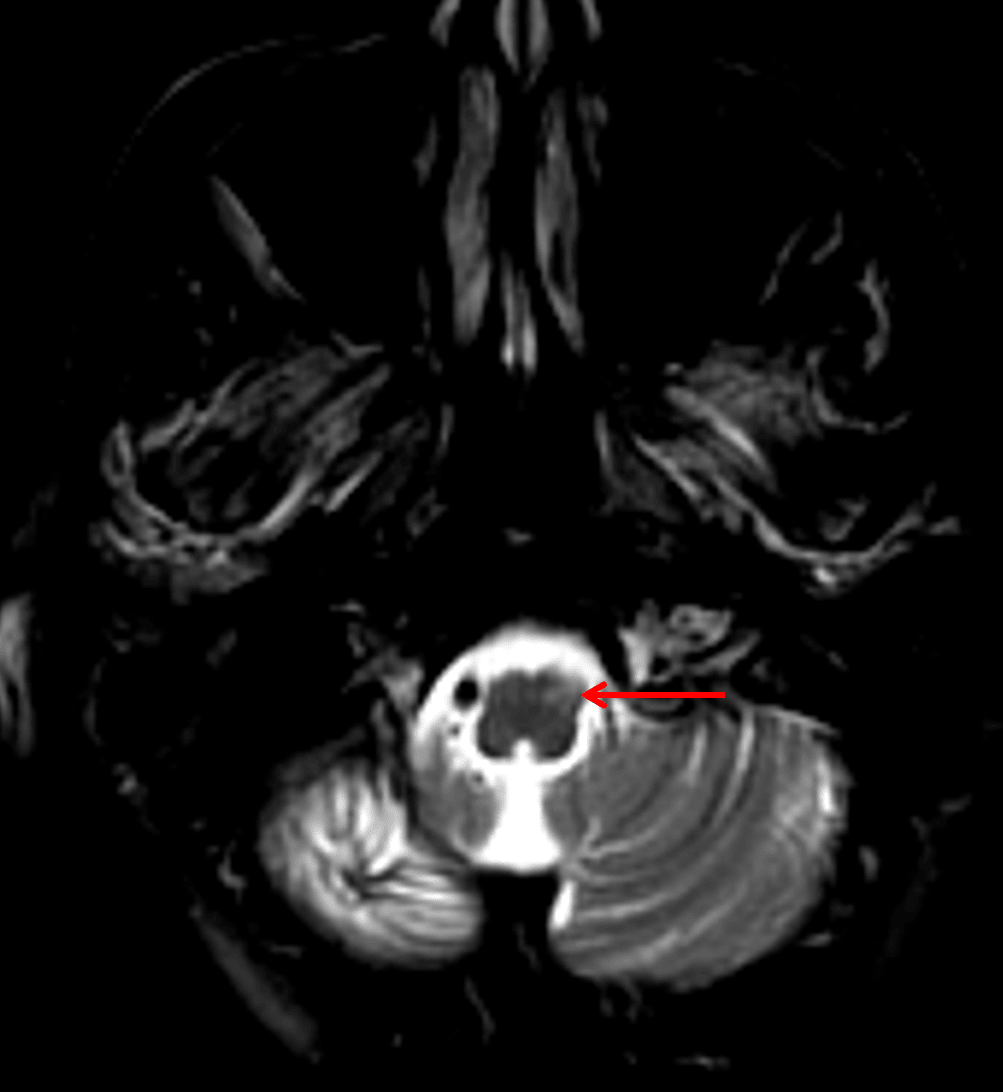

Interestingly, this patient later developed hypertrophic olivary degeneration (red arrow) contralateral to their dentate nucleus involvement.